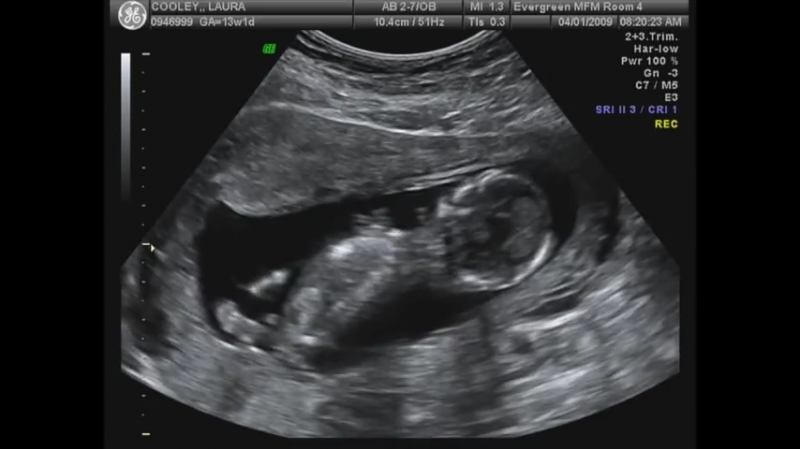

Norejau kurti nauja tema. Ja geriau butu pavadinti pagal NUB teorija.

sia teorija susidomejau gan atsitiktinai, kai vyrui pavyko pafilmuoti musu trecio …

Na pagal nub teorija ne visai taip. nes pagal sia teorija nustatuneja lb anksti, nuo 12 sav. Ten reikalingas sagitalinis vaisiaus vaizdas (vaizdas is sono, isilgai stuburo) ir esme, kad vertinamas nub organas. kuris pas berniukus issivysto i peni, pas mergaites i klitoriu. Esme sio organo uzuomazgeles kampas ir dydis.

Is nuotraukos, kurias duoda gines, laaaabai retai, kada buna pagautas reikiamas kampas. Visai kas kita, kai ziuri nufilmuota irasa. Tada, galima 80-90 proc tikslumu atspeti. O is tokios nuotraukos tik burimas, kaip su ziedu